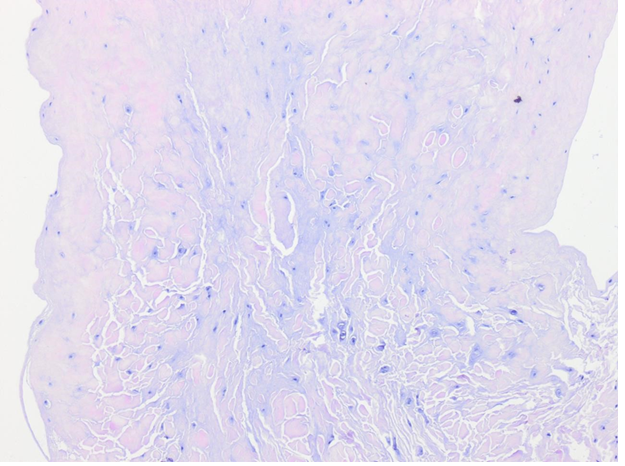

H&E stains of normal CCr and Ruptured CCr as reference

H&E Stain of ruptured CCR in study

Immunofluorescent LHR stain in ruptured CCr : Score 6/6 based on Kiefel and Kutzler 2020